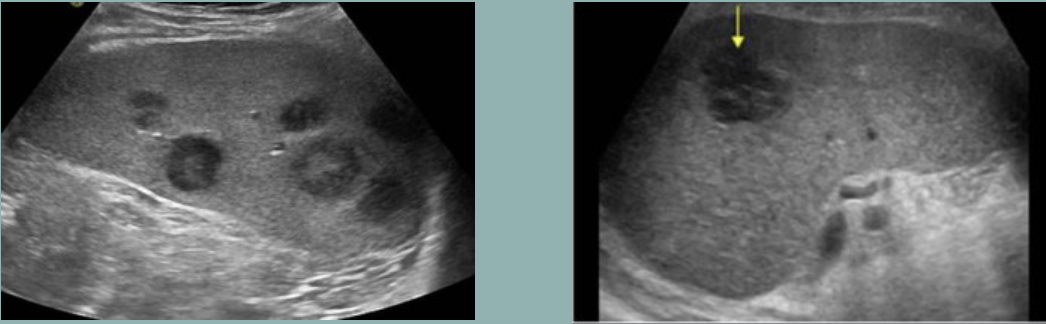

Lymphoma → cancer of lymphocytes in spleen

clinical hx: middle-aged/older adults

s/sx: unexplained fevers, night sweats, unintentional weight loss, fatigue

2D US: splenomegaly, hypoechoic lesions, enlarged LUQ lymph nodes, can small/large focal nodular lesions, diffuse or small nodular pattern

color doppler: vascular

DDX: